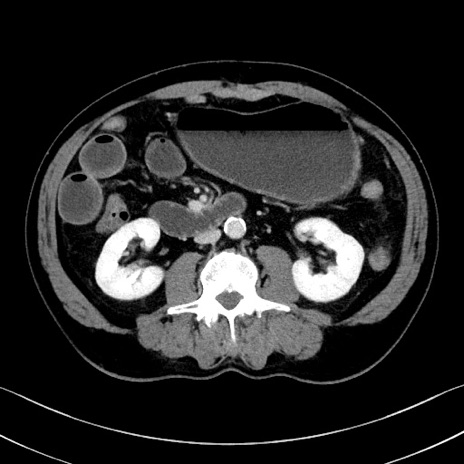

症例35(横断像)

冠状断像

【症例】70歳代 男性

【主訴】腹部膨満、嘔吐

【現病歴】昨日より腹部膨満感出現。本日増悪し、仙痛出現。嘔吐あり、受診。

【既往歴】糖尿病、胆摘後

【身体所見】BP 149/80mmHg、HR 74/min、BT 35.9℃、腹部:膨満、軟、圧痛なし。腸雑音減弱あり。上腹部正中切開瘢痕あり。

【データ】WBC 13500、CRP 1.72